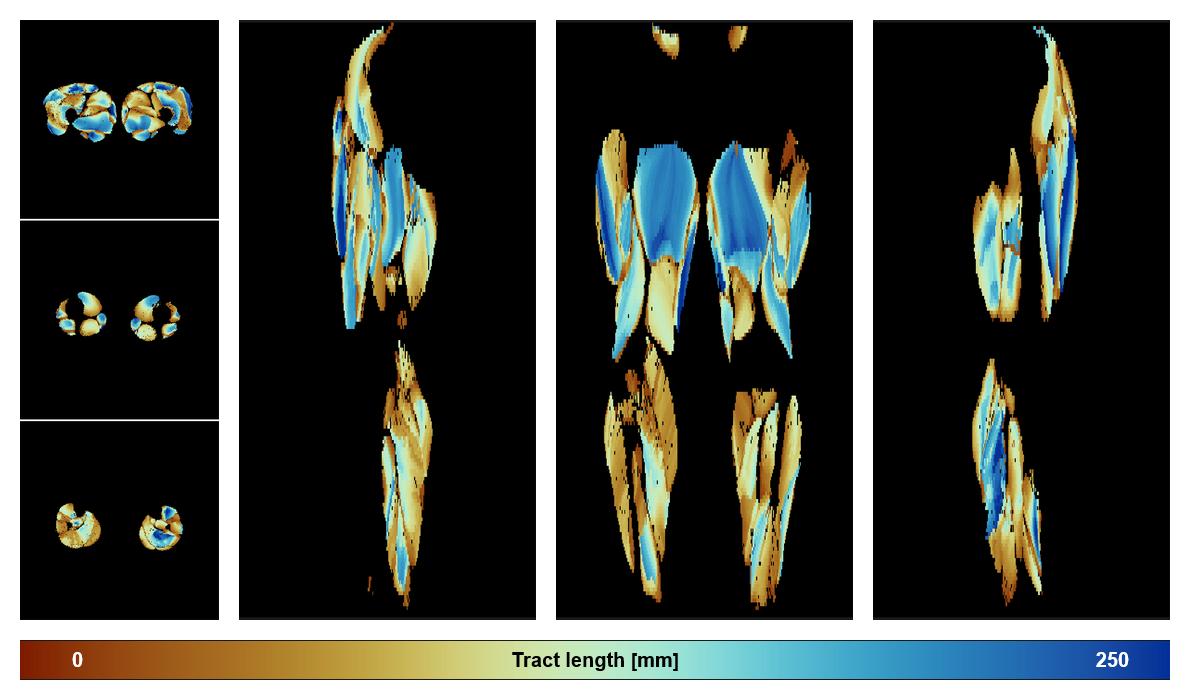

• Muscle fiber length map

Muscle fiber tract length map based on whole leg DTI based fiber tractography.